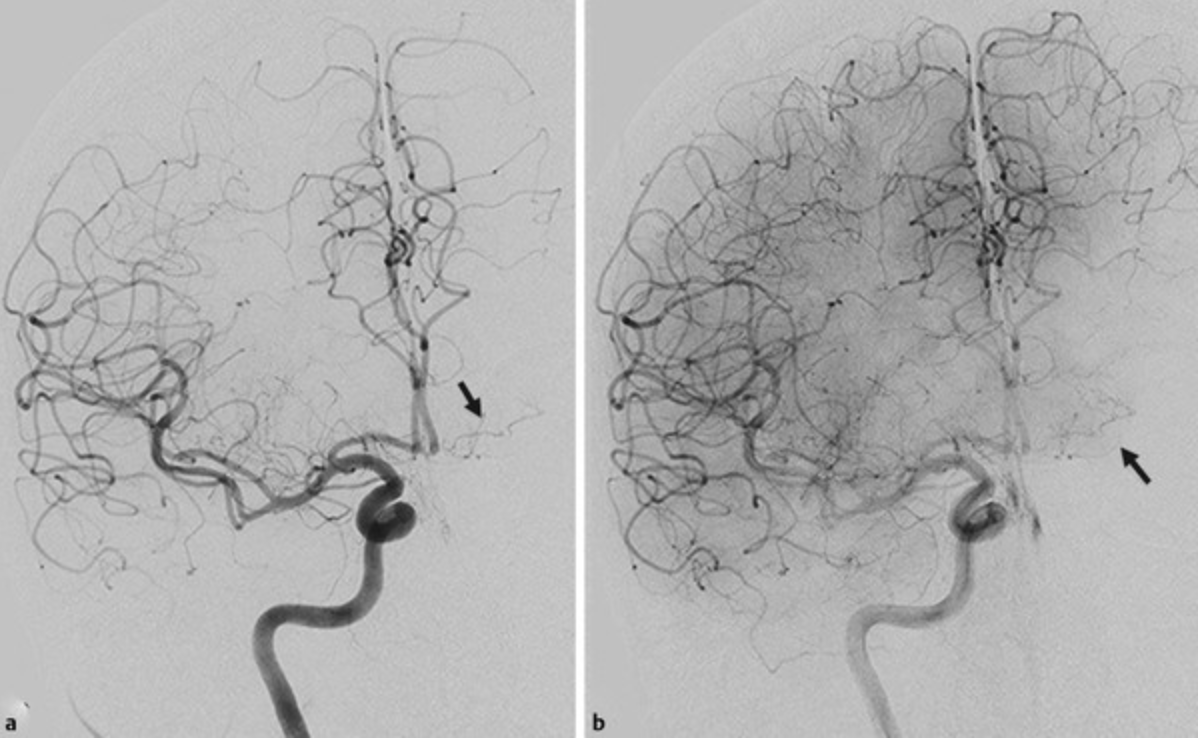

On this lateral view R ICA injection, name these two branches:

Pericallosal and callosomarginal arteries off the ACA